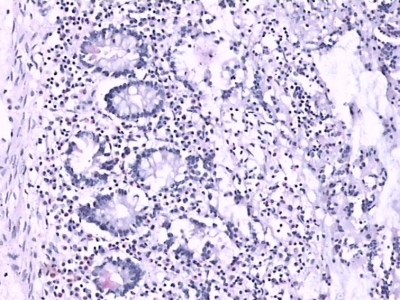

(1)增生期:病程的第1周。肠壁上的淋巴结充血水肿,有大量巨噬细胞增生,淋巴细胞明显肿胀,伤寒杆菌被单核细胞-巨细胞吞噬后大多仍在细胞内继续繁殖,并随淋巴-单核细胞散布至全身。在这一阶段,伤寒杆菌和毒素不断进入血液引起全身症状。

(2)坏死期:病程的第2周。由于细菌毒素的作用,以及巨噬细胞过度增生压迫血管,局部缺血,导致肿胀的肠壁淋巴组织发生小灶性坏死,并融合扩大成片状。

(3)溃疡期:病程的第3周。位于肠壁黏膜下淋巴集结发生组织坏死、脱落,形成沿淋巴集结长径并与肠管长轴平行椭圆形溃疡。溃疡多位于肠系膜对侧,深浅不一,一般达黏膜下层,但也有的深达肌层,甚至累及浆膜。

(4)愈合期:病程的第4周。溃疡形成后,黏膜下层出现新的肉芽组织,并被再生的肠黏膜上皮覆盖而愈合。